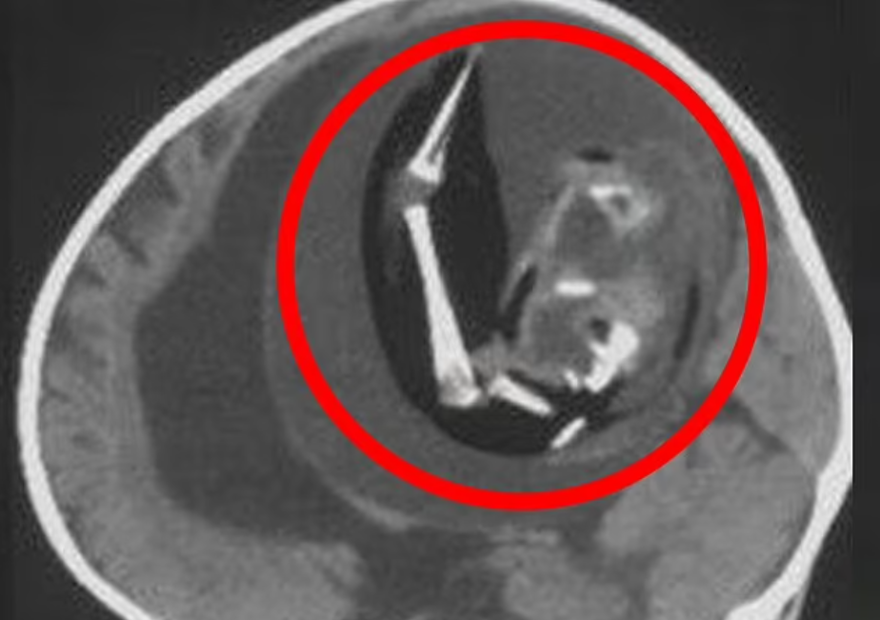

Çin'de doğmamış ikizinin fetüsü, bir yaşındaki kız bebeğin kafatasından ameliyatla çıkarıldı. 'Fetüs içinde fetüs' adı verilen oldukça nadir vakada, doktorlar fetüsün üst uzuvlarının, kemiklerinin ve hatta tırnaklarının gelişmiş olduğunu, yani kardeşinin içindeyken aylarca büyümeye devam ettiğini söyledi.Yaklaşık beş santim uzunluğundaki fetüs, ancak ebeveynler kızlarını kafası büyüdüğü ve motor becerilerinde sorunlar yaşadığı zaman doktora götürdüklerinde fark edildi.

Şangay'daki doktorlar, doğmamış ikizin fetüsünün çocuğun beyninde geliştiğini tespit etti. Çalışmanın yazarları, "Motor becerilerinde gecikmesi ve genişlemiş baş çevresi olan 1 yaşındaki bir kız çocuğunda malforme olmuş monokoryonik diamniyotik ikiz olan intraventriküler fetüs içinde fetüs (fetus-in-fetu) tespit edildi." denildi.